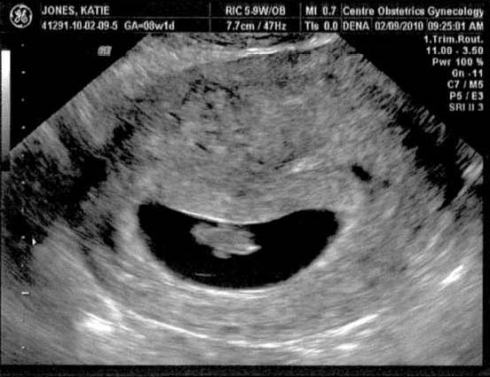

The little cahkah in the womb was measuring 1.3 cm at 7.5 weeks and the heart rate was 154. A week later, during our check up today, the cahkah was already at 2.1 cm. The doctor reminded us that second children are usually larger, and I noticed Katie cringe a little (bless her heart).

Here are a couple of early ultrasound images from last week.